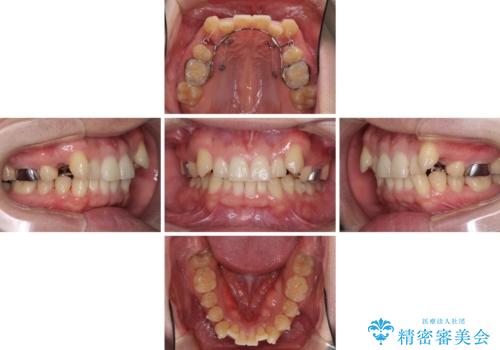

気になる八重歯を抜歯矯正で改善 補助装置を用いたインビザライン矯正

- 上顎の八重歯と前歯のデコボコを気にして来院された患者様です。

八重歯の移動量が多く、インビザライン単体での治療は困難と判断し、補助装置により八重歯移動後にインビザラインを用いることとしました。